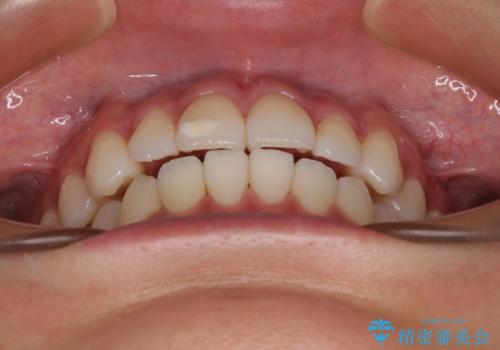

- 前歯のデコボコと奥歯の咬み合わせを気にして来院された患者様です。

右側の奥歯は、上が外側に転位した鋏状咬合を呈しており、前歯のデコボコ改善と並行して咬み合わせを改善していく必要がありました。

- 1年5ヶ月